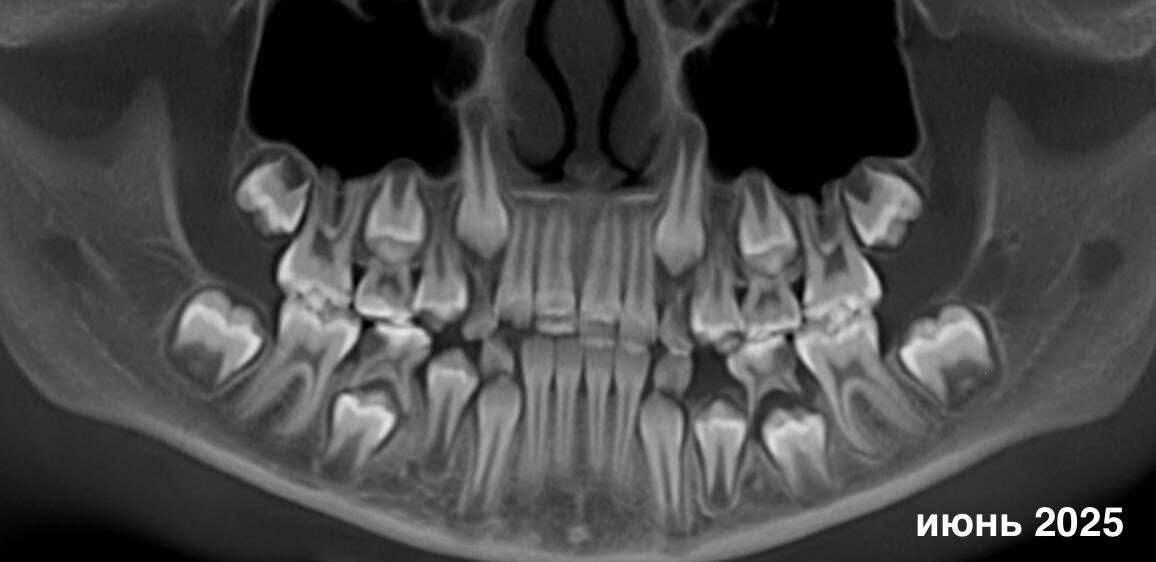

Но мы можем все исправить! История нашей юной пациентки классический пример, почему так важно наблюдение после травмы молочных зубов. Годы назад удар привел к дилацерации — искривлению коронковой части зубов формирующихся постоянных резцов. Когда зубы прорезались, стало понятно: без лечения не обойтись. Первично девочку осмотрел ортодонт (спасибо коллеге за внимательность и направление), после чего пациентка пришла ко мне. Основная задача была максимально щадящей — сохранить жизнеспособность зубов и дать корням возможность продолжить формирование. Что я сделала 👉 • Провела пульпотомию (ампутацию коронковой части пульпы) зубов 11 и 21, • Выполнила восстановление композитным материалом. Лечение было непростым: ребёнок быстро уставал. Но ее храбрость и терпение родителей дало результат. Мы сразу обсудили, что после полного прорезывания, следующий этап – коррекция реставраций, а также рекомендовали продолжить работу с другими зубами.

История нашей юной пациентки классический пример, почему так важно наблюдение после травмы молочных зубов. Годы назад удар привел к дилацерации — искривлению коронковой части зубов формирующихся постоянных резцов. Когда зубы прорезались, стало понятно: без лечения не обойтись.

Первично девочку осмотрел ортодонт (спасибо коллеге за внимательность и направление), после чего пациентка пришла ко мне. Основная задача была максимально щадящей — сохранить жизнеспособность зубов и дать корням возможность продолжить формирование.

• Провела пульпотомию (ампутацию коронковой части пульпы) зубов 11 и 21,

• Выполнила восстановление композитным материалом.

Контроль через полгода (декабрь 2025) показал то, ради чего мы всё и делали:

корни продолжают формироваться, зубы остаются жизнеспособными. Для меня это всегда самый ценный результат.